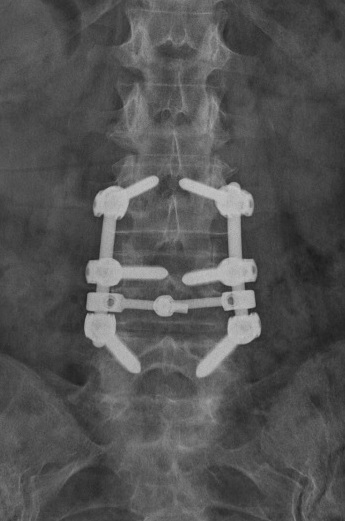

In pazienti con deficit radicolari trovano indicazione interventi chirurgici di laminotomia-foraminotomia (fig.12), in presenza di concomitanti stenosi laterali o dei forami. Interventi di artrodesi strumentata e cauta correzione della curva devono essere riservati a pazienti in buone condizioni generali (fig.13), con osteoporosi assente o non grave, con un quadro di lombalgia cronica e sintomatologia dolorosa agli arti inferiori di durata ed intensità adeguate (figg.14-15).

Peraltro, come già sopra anticipato, il continuo aumento dell'età media di sopravvivenza ed il miglioramento della qualità di vita anche in età anziana, in associazione con la continua evoluzione dei materiali di stabilizzazione (viti peduncolari a maggior tenuta, rivestite in idrossiapatite -fig.16- , a doppia filettatura, cannulate e forate per l'inserimento di cemento, ecc…), hanno determinato negli ultimi anni un aumento delle indicazioni chirurgiche in tale patologia con riscontro di ottimi risultati clinici, immediati ed a distanza (figg.17-18-19).